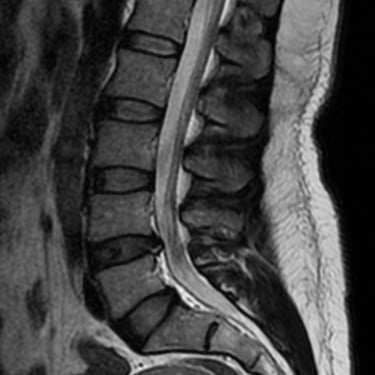

La hernia de disco lumbar se produce cuando el núcleo pulposo del disco intervertebral se desplaza y comprime las raíces nerviosas, generando dolor lumbar, ciática y debilidad en las piernas. El diagnóstico por resonancia magnética (RMN) es el método más preciso para identificar el nivel afectado y el grado de compresión nerviosa. Este estudio permite evaluar la morfología del disco, el canal vertebral y las estructuras adyacentes, orientando el tratamiento médico o quirúrgico. La detección temprana mediante RMN es fundamental para prevenir daño neurológico y planificar una intervención segura y efectiva en caso necesario.